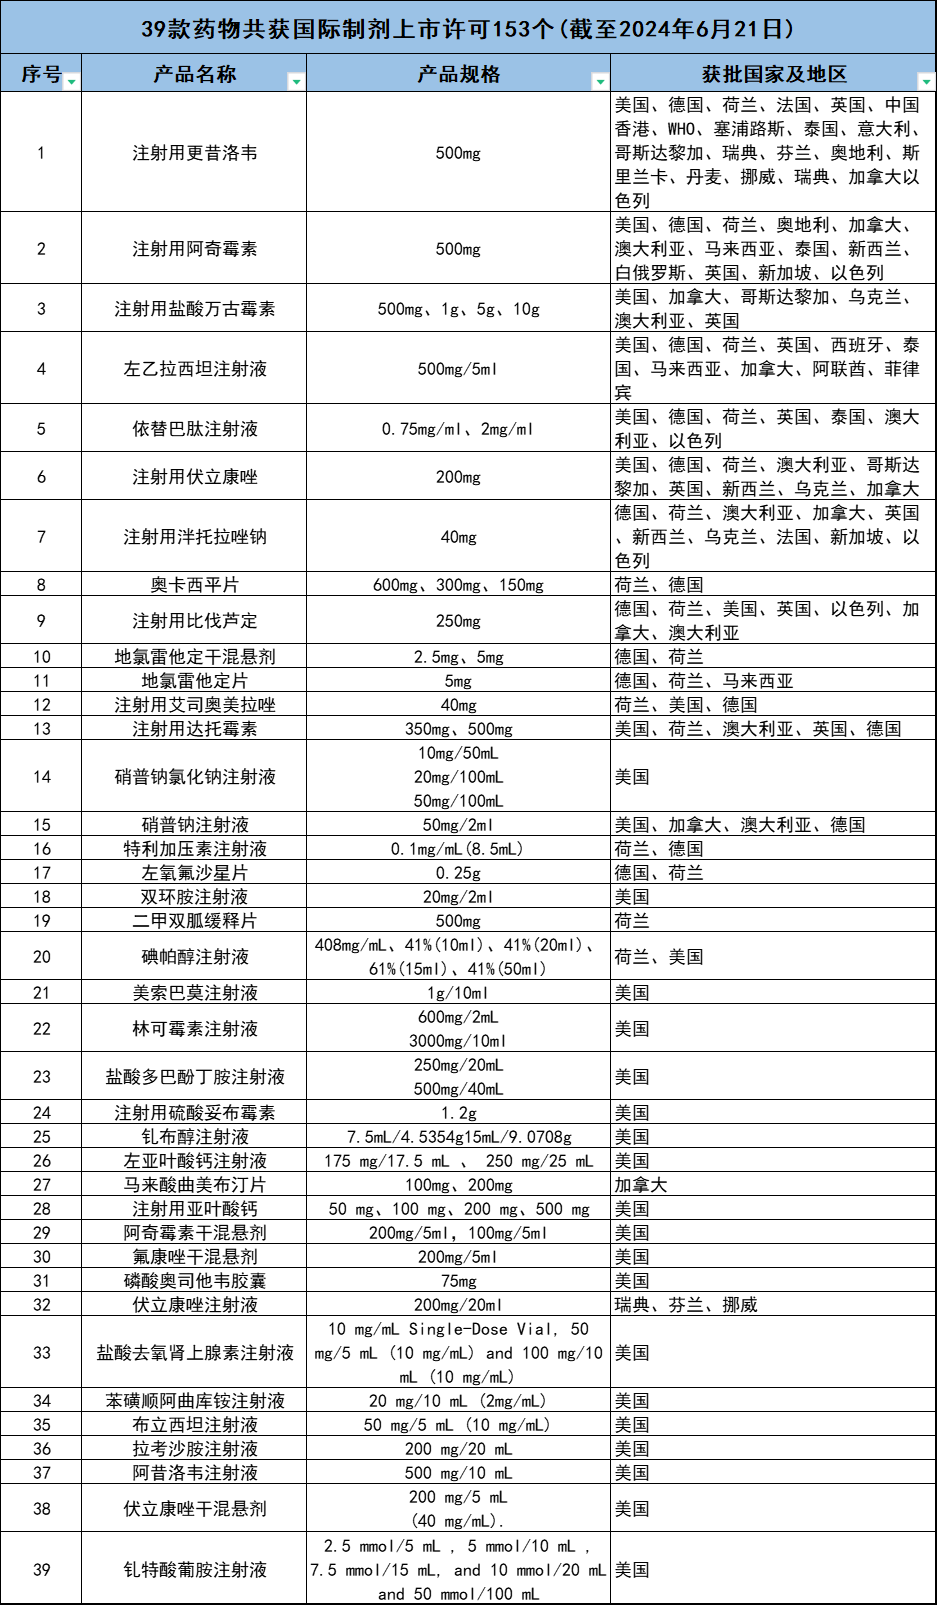

普利制药的国际化高端仿制药,普利制药从事药品国际化开拓以来,产品已销往美国、德国、法国、荷兰、英国、加拿大、澳大利亚、意大利、西班牙、丹麦、捷克、乌克兰、泰国和马来西亚等多个国家,已形成了中国制造、全球销售的国际化格局。截至2024年6月21日,39款药物共获国际制剂上市许可153个。